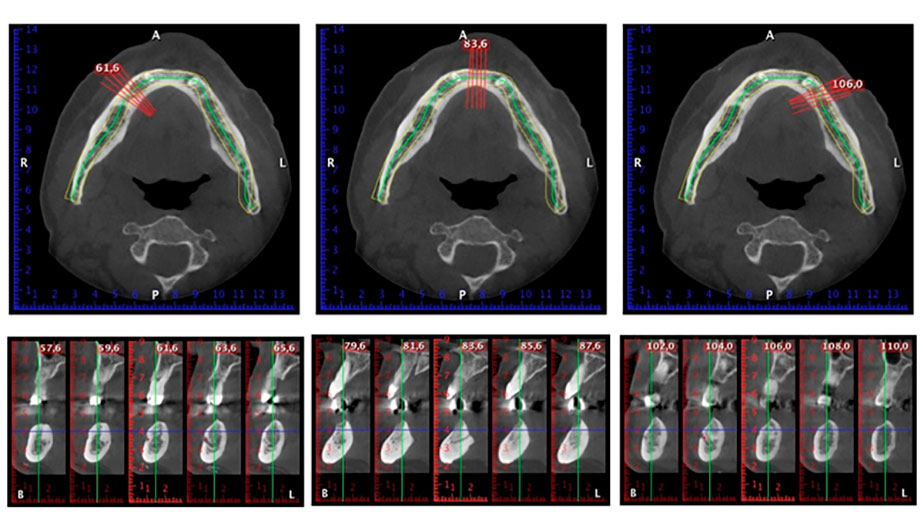

Направи се скенер с триизмерна компютърна томография (CBCT, Planmeca), за да се подпомогне планирането и да се намалят рисковете. Той показа, че качеството и количеството на наличната кост са достатъчни за операцията и имедиатното възстановяване, използвайки Fast & Fixed метод. Следвайки протокола за тази концепция, имплантите са поставени на 35, 32, 42 и 45 позиция. Ангулирането на дисталните импланти до 45° промени профила в задната зона и осигури по-голяма поддръжка в многоъгълната зона (Фиг. 3).